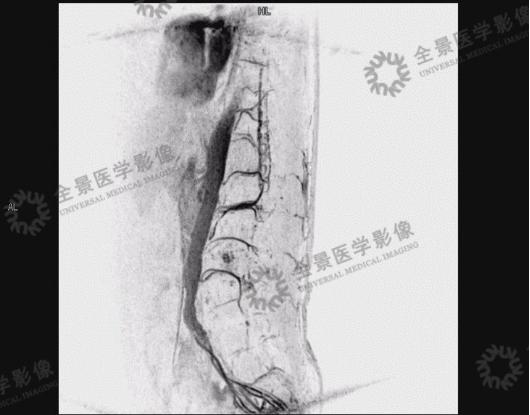

案例二

男,58 岁。右下肢乏力逐渐加重 1 年,双下肢无力 1 月。

2020 年 1 月 8 日,肌电图示:腰骶段脊髓神经损害。

DSA 结果:硬脊膜动静脉瘘。